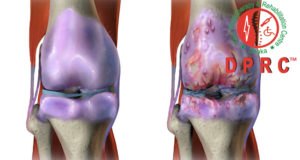

“অষ্টিওআথ্রাইটিস অব নি” এবং চিকিৎসা।

অষ্টিওআথ্রাইটিস অব নি কি? “অষ্টিওআথ্রাইটিস অব নি” বা হাটু ব্যথা, শুধু ক্ষয় জনিত রোগেই নয় এর কারন বিভিন্ন। তবে সবচেয়ে বেশি ...

অস্টিওআর্থ্রাইটিস হওয়ার কারণ: ক) বয়সের কারণে বয়স বাড়ার সাথে সাথে ক্রমাগত ব্যবহারে কার্টিলেজের ধীরে ধীরে ক্ষয় হতে থাকে এবং এই ...